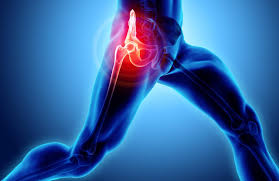

1. 고관절이란?

고관절은 골반과 대퇴골이 만나는 관절로, 인체에서 가장 크고 강한 관절 중 하나입니다. 이 관절은 공 모양의 대퇴골 두부와 그것을 감싸는 비구라는 구조로 구성되어 있으며, 몸의 체중을 지탱하고 걷기, 뛰기, 앉기, 서기 등의 동작을 가능하게 합니다. 고관절은 연골, 인대, 점액낭, 근육 등 다양한 조직이 유기적으로 작용하여 움직임과 안정성을 동시에 제공합니다.